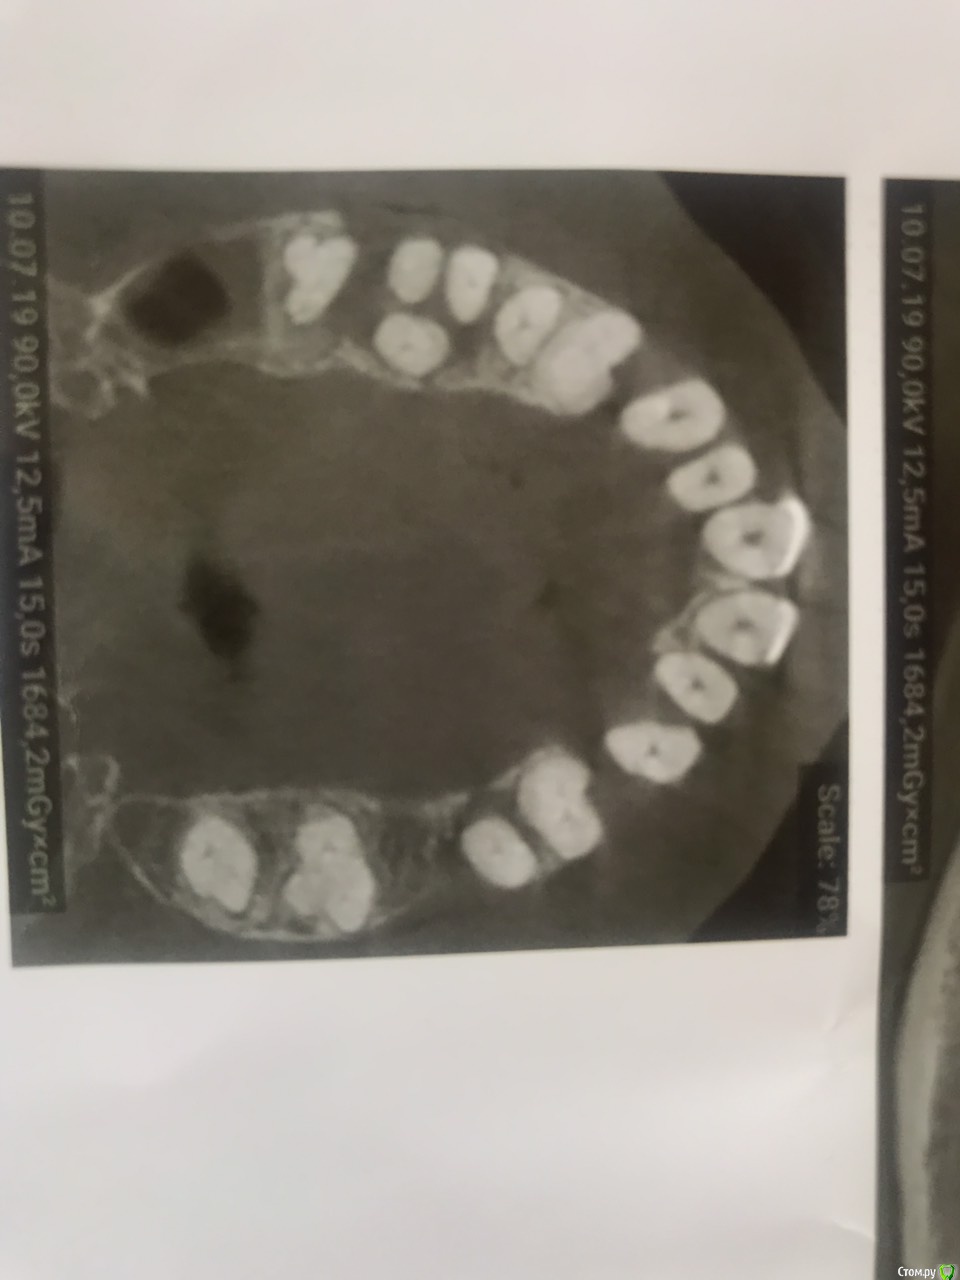

leyla-night Опубликовано 3 августа, 2019 Поделиться Опубликовано 3 августа, 2019 Добрый день! Очень нужен совет. Ходила в стоматологию к терапевту. сказали есть подвижность некоторых зубов. Сделали чистку. зубы стали остальные шататься, даже те которые не шатались, а один теперь болит, а я пришла у меня ничего не болела. Сказали сделать три Д снимок, сделала. Сообщили, что 7 зубов нужно удалять. Но заниматься мной не стали. Сказали, сами выпадут потом поставите челюсть. Я инвалид 1 группы не могу сидеть в кресле стоматолога. До 2013 года меня принимали в моей коляски и пломбы ставили и чистку делали все было нормально. Сейчас стоматологии стали еще лучше, но я не могу получить помощь. Посоветуете пожалуйста по моему снимку. можно, мне как то помочь., Ссылка на комментарий

hogsmeed Опубликовано 3 августа, 2019 Поделиться Опубликовано 3 августа, 2019 Здравствуйте Подвижность зубов после чистки обычное явление(вернее ощущение этой подвижности). По снимку действительно нужно убирать зубы, спасти их затруднительно, дальше либо имплантация, либо съемный протез). Принять пациента в коляске вообще не проблема, установки фирмы Adec например (довольно популярной фирмы) оборудованы подголовником, который позволяет лечить в вашем кресле. Ссылка на комментарий